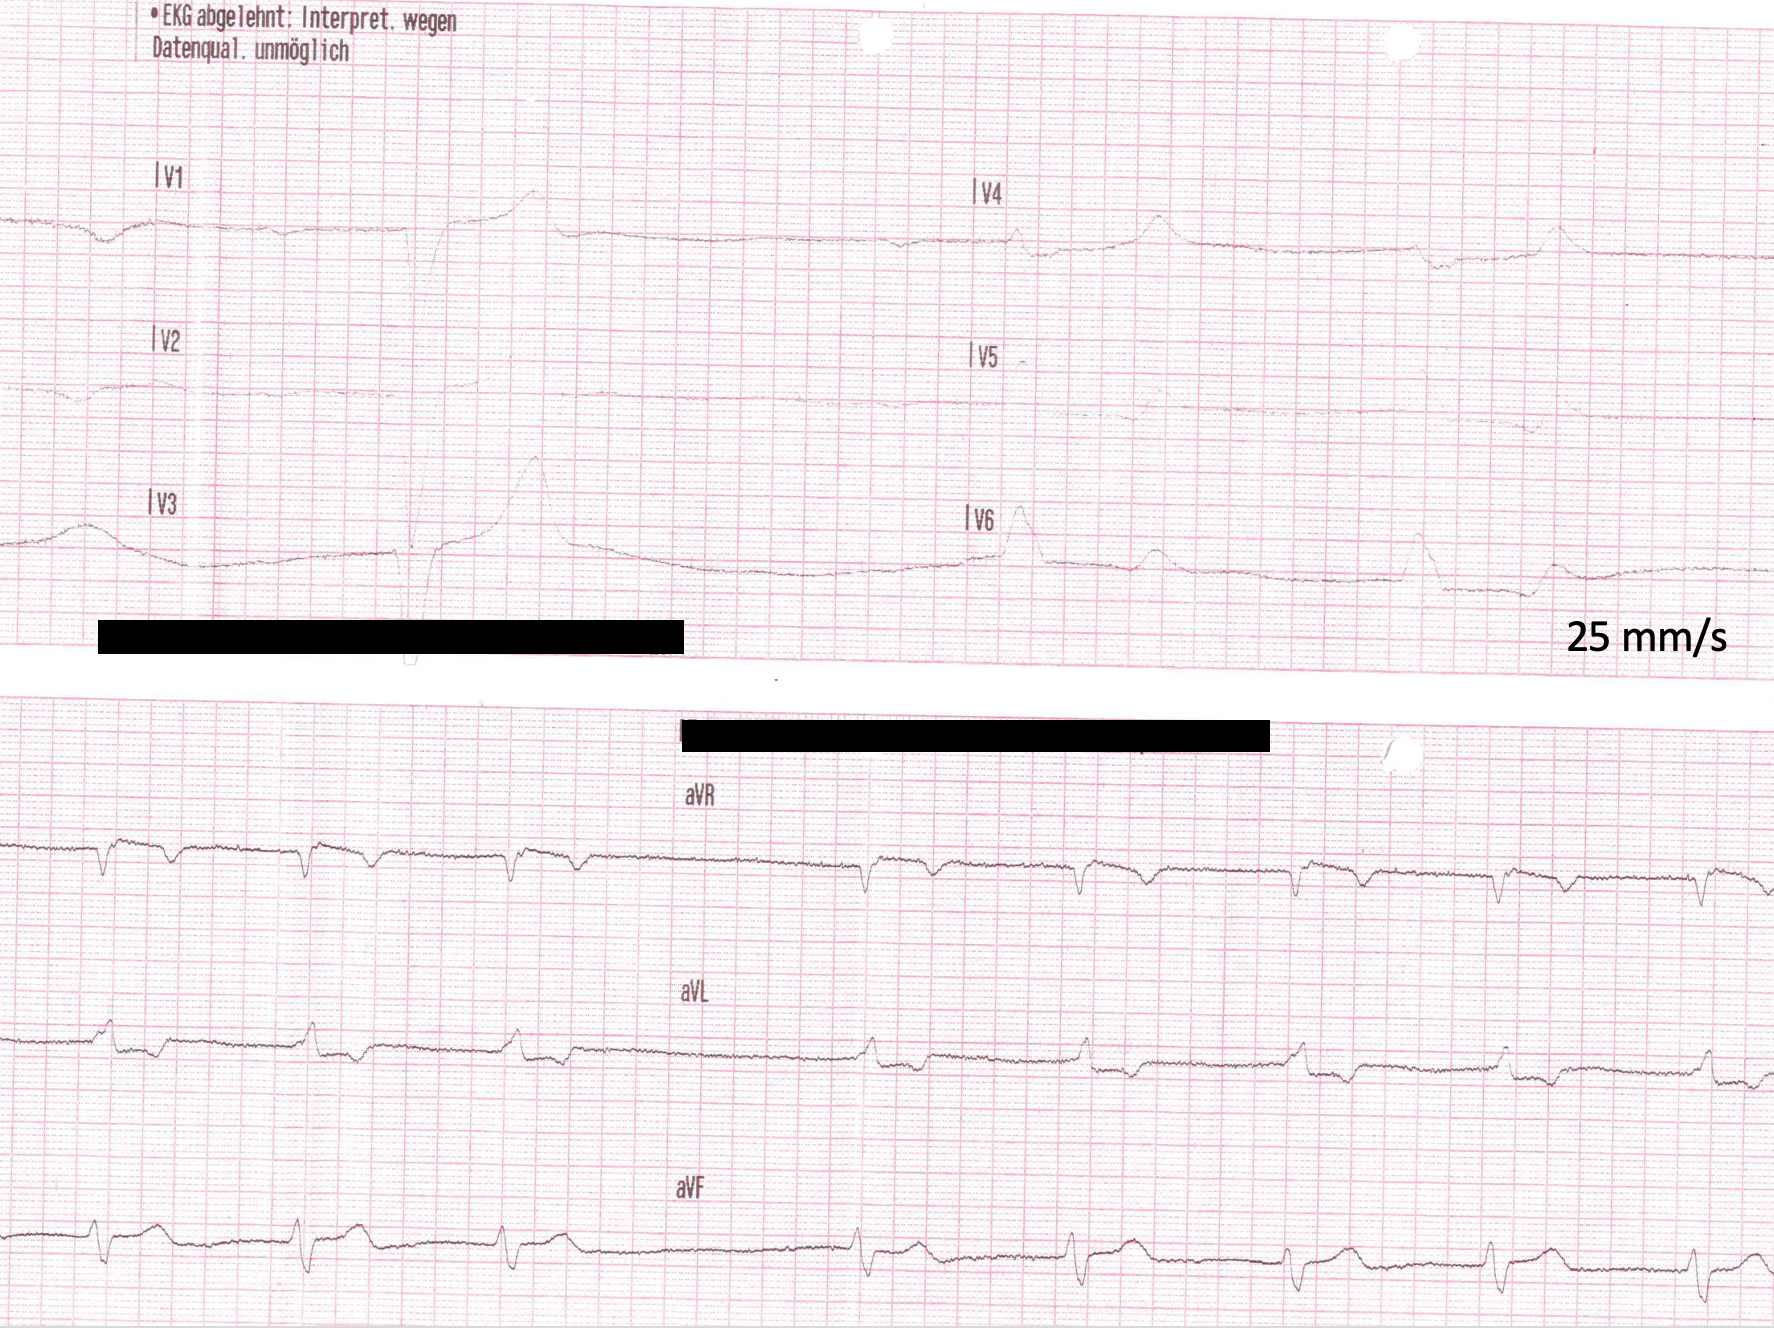

image-10